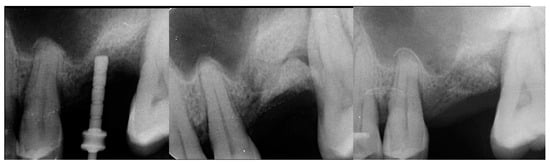

A 57-year-old male patient presented requesting replacement of a missing maxillary left 1st molar. A radiograph was obtained with a marker to evaluate the available crestal height present (Figure 15 left). The patient was informed that grafting would be needed to increase crestal height, then following healing a crestal sinus lift would be performed with simultaneous implant placement with restoration following integration.

Figure 15.

Radiograph of the initial site in preparation for implant treatment demonstrating minimal bone height available with a defect at the distal aspect of the site (left), of the site following EthOss grafting of the crestal graft (middle) and following 10 weeks of graft healing (right).

The consent form was reviewed with the patient and signed. Local anesthetic was administered and a crestal incision was made with a flap at the site to expose the ridges top. EthOss graft material was prepared as previously described and placed into the defect on the crest to level the crest with the mesial bone distal to the premolar (Figure 15, middle).

The patient returned at 10 weeks and a radiograph was obtained to evaluate the height of the crest (Figure 15 right). A crestal sinus lift was performed following the previous steps described in case 1 and 2 and a 4 × 8.5 mm Anyridge implant was placed with a cover screw.

The patient returned at 10 weeks and the implant was uncovered. An impression was obtained, and a healing abutment placed on the site. A radiograph was obtained to verify the healing abutment was seated, which demonstrated conversion of the graft material to immature host bone (Figure 16, right). The restoration was returned from the lab and the patient was returned to complete the treatment. The healing abutment was removed (Figure 17, left) and the restoration was inserted (Figure 17, middle). A radiograph was obtained to verify complete seating of the restoration to the implant (Figure 17, right). Radiographically, the previously grafted area at the crest and sinus blended well with the surrounding host bone.

Figure 16.

Radiograph following crestal sinus augmentation with EthOss and implant placement (left) and at uncovery and healing abutment placement after 10 weeks of implant placement demonstrating conversion of the graft material to host bone (right).